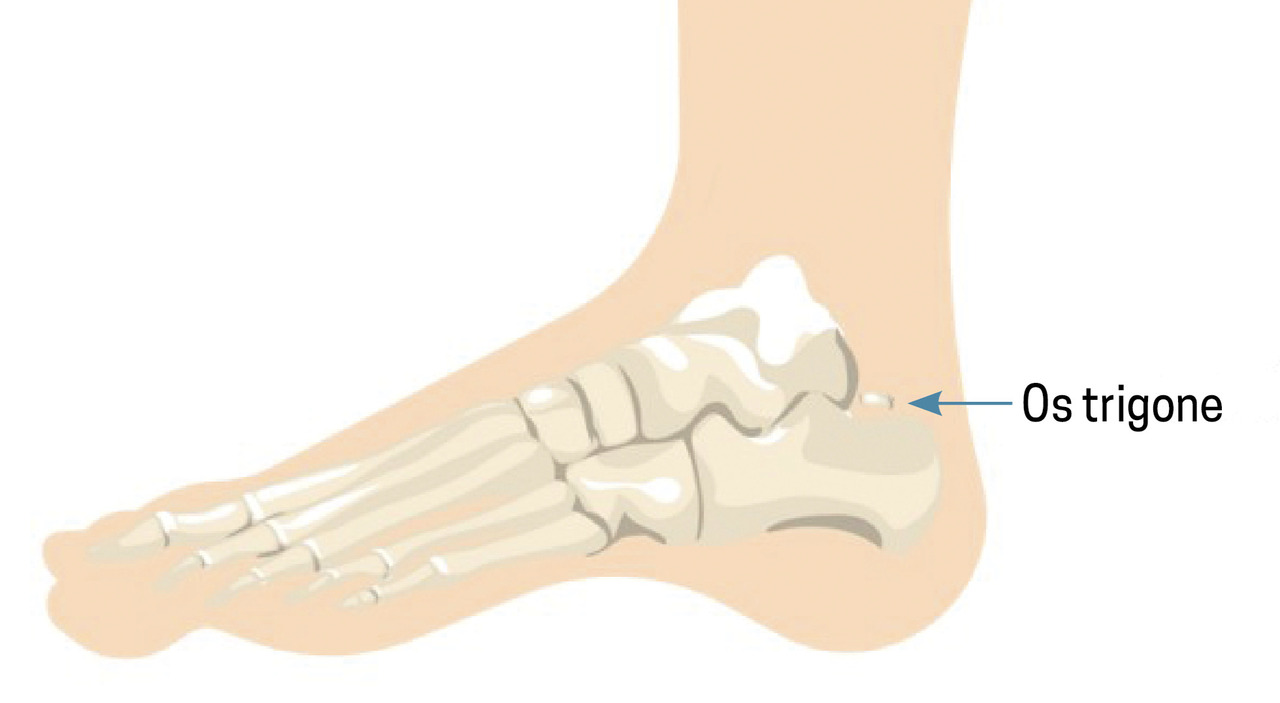

Miguel, 41 ans, consulte à la suite d’une chute mal réceptionnée dans le bassin d’un toboggan de parc aquatique. Depuis, il a une douleur avec impotence fonctionnelle du pied droit. À son arrivée au cabinet, il a une attitude antalgique avec claudication à droite. L’examen clinique révèle une douleur reproductible lors de la flexion plantaire et à la palpation du talon. Aucun trouble sensitif ni vasculaire n’est observé. Le mollet est souple et indolore, sans signe de Thompson. Un bilan radiographique est effectué, révélant la fracture d’un os trigone surnuméraire (fig. 1, flèche).

L’os trigone est un os dit surnuméraire situé derrière le talus (fig. 2). Il résulte de la non-fusion du versant postérieur du talus entre l’âge de 7 et 13 ans.1 Sa présence peut entraîner des douleurs à la flexion plantaire forcée, piégeant cet os entre le calcanéus et le tibia – c’est le syndrome de l’os trigone (fig. 3).2